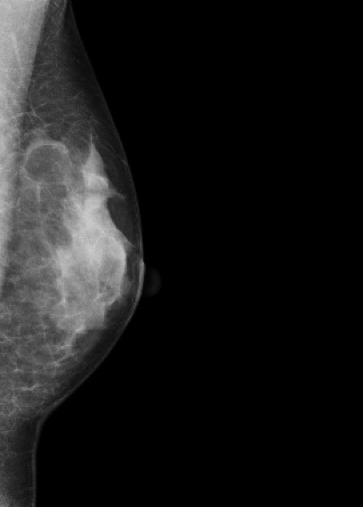

マンモグラフィ検査

装置の紹介

当院では2016年5月に乳房撮影装置

MAMMOREX Pe・ru・ru DIGITAL

(キヤノンメディカルシステムズ)を導入しました。

FPDを搭載した装置で、解像力やコントラストが向上し微細な石灰化や腫瘤をより鮮明に描出することが可能です。検査は健診棟の女性専用エリア内に併設されたマンモグラフィ専用の検査室で行っており、安心して検査を受けていただけます。撮影はNPO法人日本乳がん検診精度管理中央機構の認定を受けた女性技師が担当します。

マンモグラフィとは

専用の装置を用いて行う乳房のX線撮影のことです。 マンモグラフィは視触診では分からない早期乳癌の微細な石灰化や、触っても分からない小さなしこりの描出に優れています。

*当院では左右の乳房それぞれで2方向の撮影(CC撮影・MLO撮影)を計4枚行います。

*2方向から撮影を行うことで乳房全体をまんべんなく写すことができます。

圧迫の必要性

厚みのある乳房の中にはたくさんの乳腺や脂肪などが重なって存在しています。

これらを均等に伸ばし組織同士の重なりを分離することで、小さなしこりや石灰化の粒をより見つけやすい画像にすることができます。

*実際に乳房を圧迫する時間は1枚の撮影で数十秒程度です。

画像1枚目:圧迫なし、画像2枚目:圧迫あり